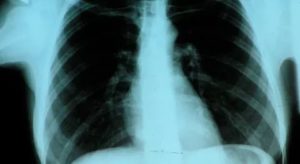

Рентген легких курильщика и здорового человека

Чем отличаются легкие курильщика и обычного человека на разных этапах курения? Давайте рассмотрим этот вопрос:

Здоровые легкие имеют розовый цвет, дольчатый рисунок в форме пирамидок. Дольки поделены между собой перегородками, состоящей из соединительной ткани, по которой проходят вены и лимфатические сосуды.

Каждый снимок сделанный рентген обследованием несет в себе массу информации. Можно определить патологию и заболевания различного вида, его степень и выраженный характер.

Последствия, к которым может привести долгое курение, могут обнаружиться на флюорографических снимках. Перед флюорографией курить можно. Сигарета, выкуренная перед началом процедуры не повлияет на состояние легких на снимке. Однако следует помнить, что курильщикам рекомендуется проходить исследование чаще, чем людям без вредной привычки.